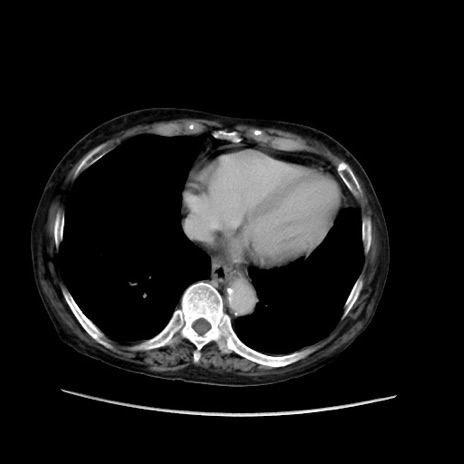

症例31(横断像)

【症例】80歳代 女性

【主訴】腹部膨満感

【現病歴】他院にて肝硬変にてフォロー中。1週間前から便秘、腹部膨満感、臍部腫瘤あり受診となる。

【既往歴】肝硬変

【身体所見】腹部膨隆あり、皮膚変化なし、疼痛なし。

【データ】WBC 4600、CRP 0.25